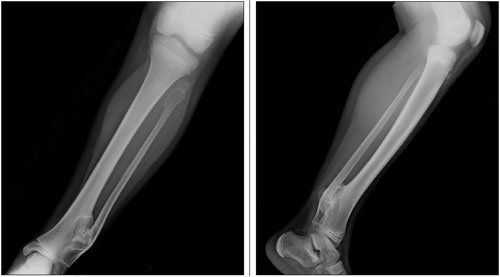

A 14-year-old girl with systemic lupus erythematosus (SLE) was evaluated for worsening left leg pain of 1 week’s duration. A month earlier, she had presented with left knee arthritis and a vasculitic rash; the antinuclear antibody titer was positive. In addition, she had leukopenia, myositis, hypocomplementemia, and mild proteinuria.